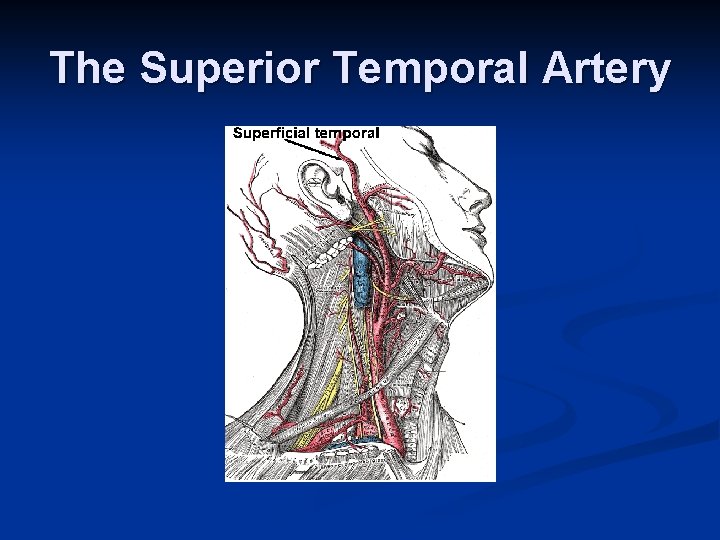

Superficial temporal artery: Terminal branch of ECA. Supplies skin over frontal and temporal regions of scalp. The superior temporal artery, which can be palpated just anterior to the pinna of the ear, is sometimes examined using duplex ultrasound in patients with suspected temporal arteritis. n TEMPORAL TAP METHOD

The Superior Temporal Artery